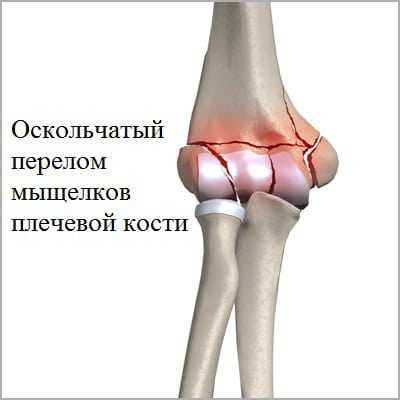

- травмы чрезмыщелковые, межмыщелковые. Это самые часто диагностируемые виды переломов, обычно возникающие при сильном ударе в локоть. Поддерживающие надмыщелки костные структуры разрушаются, что становится причиной изменения соотношения костей. Для таких травм характерно серьезное повреждение хрящевых тканей, восстановление которых является сложной задачей. После репозиции суставных элементов они крепятся винтами и пластинами до полного их сращения. Это не станет ограничением для постепенной разработки сустава.